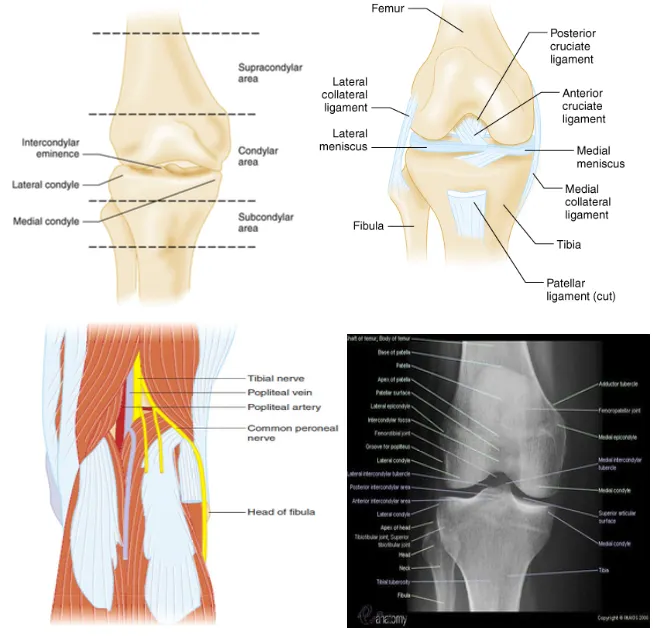

A. Anatomy

Tintinalli 9th, p1850, Fig 274-1, 2, 3

Four ligament of knee : ACL, PCL, MCL, LCL

Popliteal fossa : Popliteal artery & vein, common peroneal nerve, tibial nerve